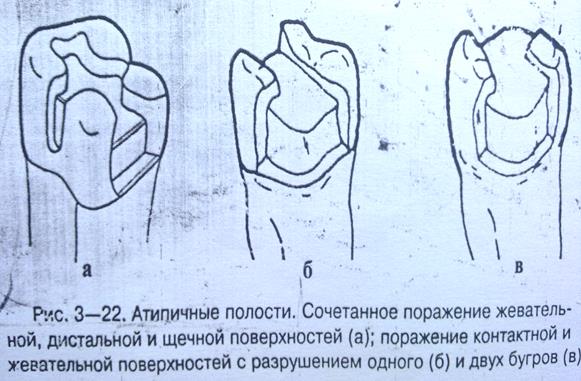

Препарирование кариозных полостей III класса: пошаговое руководство с фото